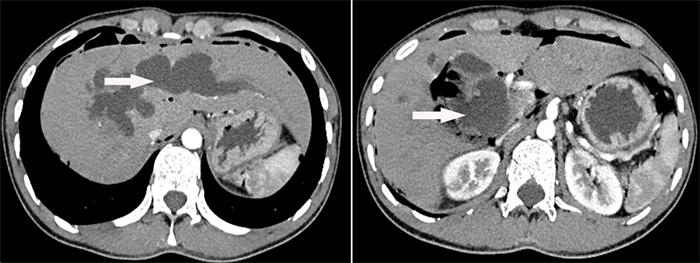

腹部增强CT显示肝内外胆管囊状病变

为尽快解除病痛,早日回归正常生活,主管医生与患者及患者家属就该疾病进行了详细沟通和交流,进行了腹部增强CT、MRCP等相关检查,明确了病因和疾病位置,患者诊断为先天性胆管扩张症(Ⅳ型)、肝内外胆管结石,并进行了住院治疗。